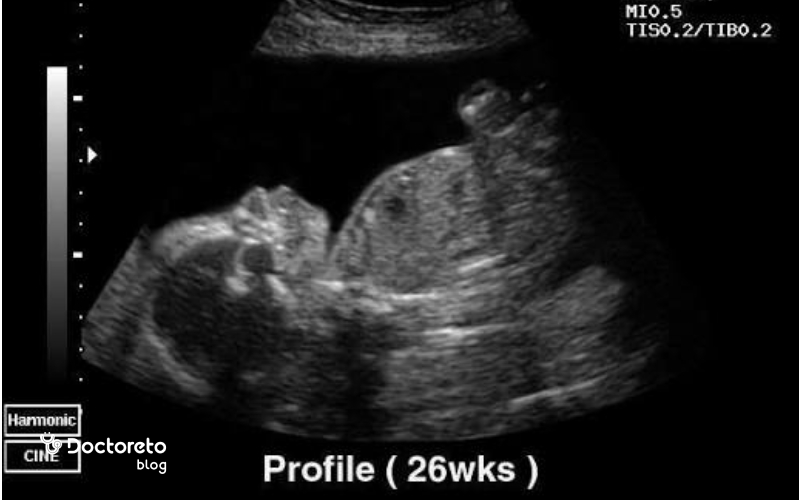

در هفته ۲۶ بارداری جنین چه شکلی است؟

همانطور که گفتیم در هفته بیست و ششم بارداری اندازه جنین تقریبا به ۲۳٫۵ سانتیمتر میرسد. چربی زیر پوست جنین در حال افزایش است، به همین دلیل جنین افزایش وزن داشته و چاق میشود. چروک پوست هم بهمرور برطرف خواهد شد. پلک جنین باز میشود و میتواند به اطراف نگاه کند. برای تعیین رنگ چشم هنوز رنگدانه کافی در عنبیه چشم وجود ندارد. عکسالعمل جنین به صداها و نور بیشتر میشود؛ مدام تکان میخورد و لگد میزند.

در هفته بیستوششم بارداری، جنین حدود ۳۵ سانتیمتر قد و نزدیک به ۹۰۰ گرم وزن دارد. اندامهای حیاتی او مانند ریهها، مغز و سیستم عصبی در حال تکامل هستند و حرکاتش منظمتر و قابلتشخیصتر شده است. پوست جنین هنوز نازک و چیندار است، اما بهتدریج با افزایش چربی زیرپوستی صافتر میشود. چشمان او اکنون میتوانند به نور واکنش نشان دهند و گوشها قادرند صداهای بیرونی مانند صدای قلب مادر یا موسیقی را بشنوند. همچنین، جنین در این هفته تنفس را بهصورت تمرینی انجام میدهد تا برای زندگی خارج از رحم آماده شود.

در هفته ۲۶ بارداری (۲۴ هفته پس از لقاح)، ابروها و مژههای جنین شکل گرفتهاند. چشمهای او نیز تکامل یافتهاند، اما ممکن است تا دو هفته دیگر باز نشوند. در این زمان، طول جنین از سر تا نشیمنگاه حدود ۲۳۰ میلیمتر (۹ اینچ) و وزن او نزدیک به ۸۲۰ گرم (۲ پوند) است.